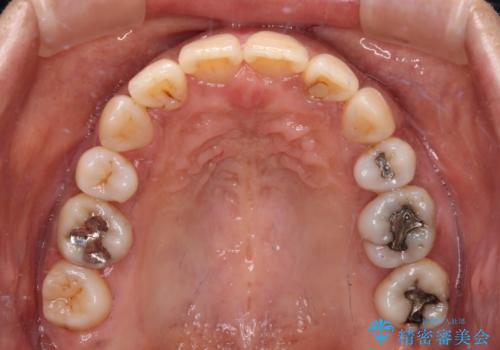

抜歯矯正により口元が引っ込みすぎて、ほうれい線が顕著となるのではないかと心配しておりましたが、矯正後にほうれい線が気になることはなく、口元もすっきりとした感じになりました。